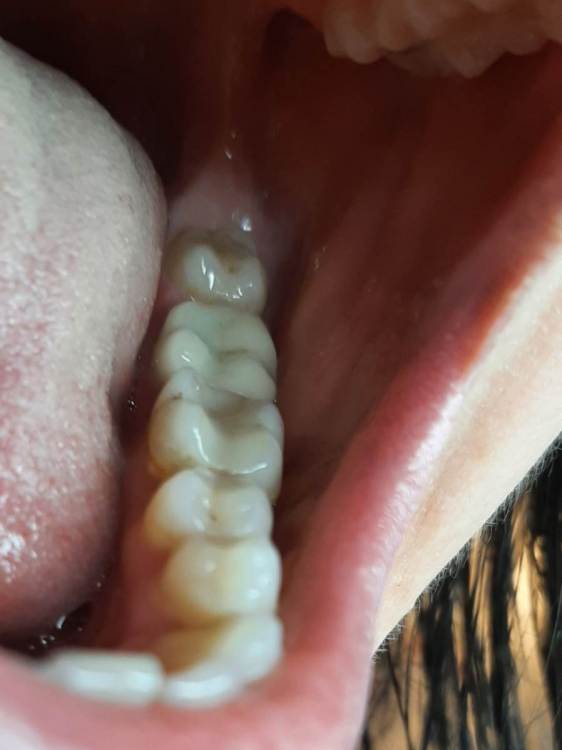

Лана-Лана Опубликовано 6 декабря, 2021 Поделиться Опубликовано 6 декабря, 2021 (изменено) Добрый день. Установили цирконевую коронку на нижнюю семёрку, при примерке я заметила что коронка низкая , но врач убедила что все впорядке типа мой зуб такой и был, самый последний бугор на контакте с восмым зубом с язычной стороны чуть ли не на уровне десны. Теперь когда жуешь и туда попадает что то твердое мясо, яблоко очень больно десну .. я сказала об этом ортопеду но она говорит что по другому не сделать, и предлагает вырвать восьмёрку и засчет этого опустится десна, но это же не выход , да и не хочу я ее удалять, раньше у меня с моим натуральным зубом таких проблем не было.... посмотрите пожалуйста снимки зуба до и фото после, действительно ли у меня был такой низкий зуб? Или это портак? На фото во рту видно что он ниже восьмёрки а край с язычной стороны ещё ниже...и если это плохо сделанно? Можно ли просить переделки ведь он ещё на гарантии? Или это проблемно снять? И что вообще в таких случаях делать если ортопед отказывает в переделке? Писать претензию? Изменено 6 декабря, 2021 пользователем Лана-Лана Ссылка на комментарий